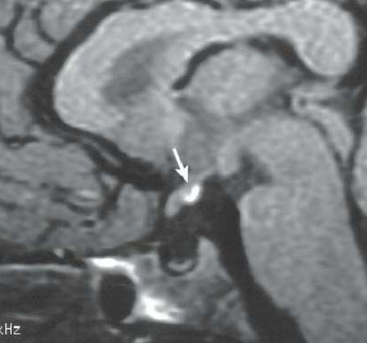

- Migration ectopique de l’hypersignal T1 spontané de la post-hypophyse

Post-hypophyse posthypophyse ectopique ectopie pituitare postérieure antérieure anthypophse antéhypophyse hpyoph anté-hypophyse neurohypophyse neuro-hypophyse ectopie panhypopituitaire pan-hypopituitarisme inssufisance pituitaire globale